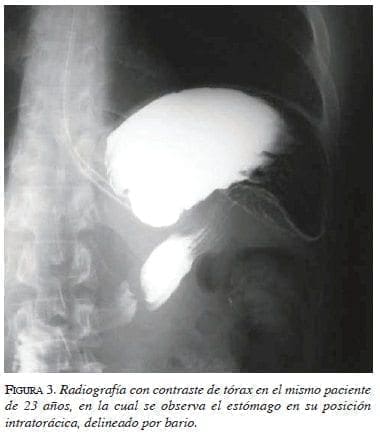

Se ha descrito el llamado “signo de la víscera pendiente”, que se produce porque los pacientes se encuentran en posición supina cuando se toma la TC; cuando el diafragma está roto, las vísceras herniadas pierden el soporte posterior que les brinda el diafragma y caen a una posición “pendiente”, apoyándose sobre las costillas posteriores. Al lado derecho, habitualmente el tercio superior del hígado no se encuentra apoyado contra la pared posterior del tórax cuando el diafragma se encuentra intacto. Al lado izquierdo, el estómago y el intestino generalmente no se apoyan en las costillas de la pared izquierda del tórax cuando el diafragma se encuentra intacto, y el estómago o intestino no se encuentran posteriores al bazo. Consecuentemente, el signo de la víscera pendiente se encuentra presente en el lado derecho cuando el tercio superior del hígado se apoya contra las costillas derechas y, en el lado izquierdo, cuando el estómago o los intestinos se apoyan sobre las costillas izquierdas a la altura de la décima vértebra torácica. La tasa de diagnóstico mediante la aplicación de este signo radiológico, se ha incrementado a 90 % o más, con un valor diagnóstico de 1. Este signo se observa en el 100 % de los casos con lesión del diafragma izquierdo y en 83 % de los pacientes con lesiones derechas20,21 (figuras 4 y 5). Los cortes sagitales y coronales en las reconstrucciones de la TC de múltiple corte, permiten observar el estómago o los intestinos herniados dentro del tórax, como se observa en la figura 6.